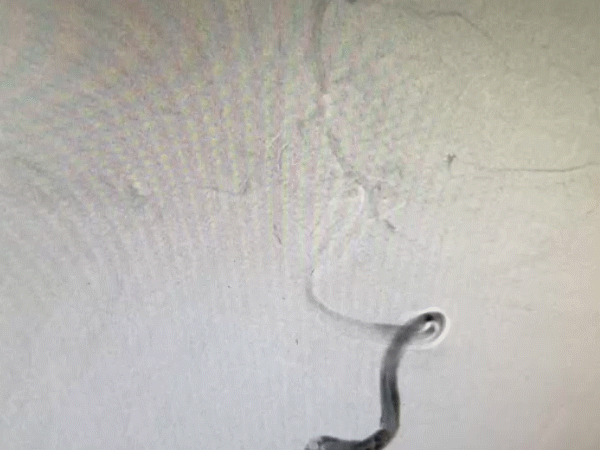

导引导管到位,导丝通过病变。

导丝怎么扩【载药时代 球扩天下】NOVA DES®颅内药物洗脱支架在颅内富穿支区域使用体会二例!_https://www.jmylbn.com_新闻资讯_第14张

导丝怎么扩【载药时代 球扩天下】NOVA DES®颅内药物洗脱支架在颅内富穿支区域使用体会二例!_https://www.jmylbn.com_新闻资讯_第15张

球囊扩张后。